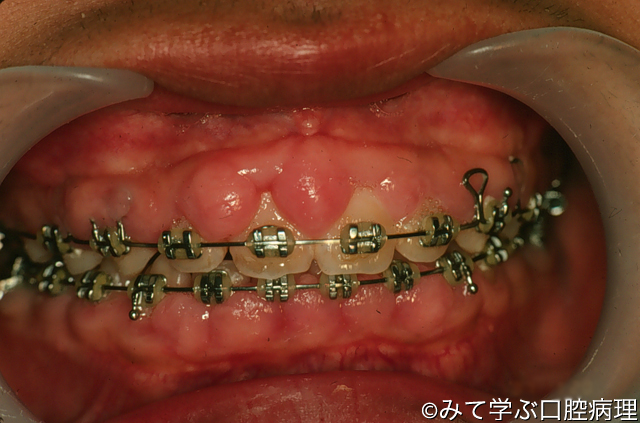

歯肉増殖症

歯肉乳頭部とその周囲の歯肉の腫大がみえる